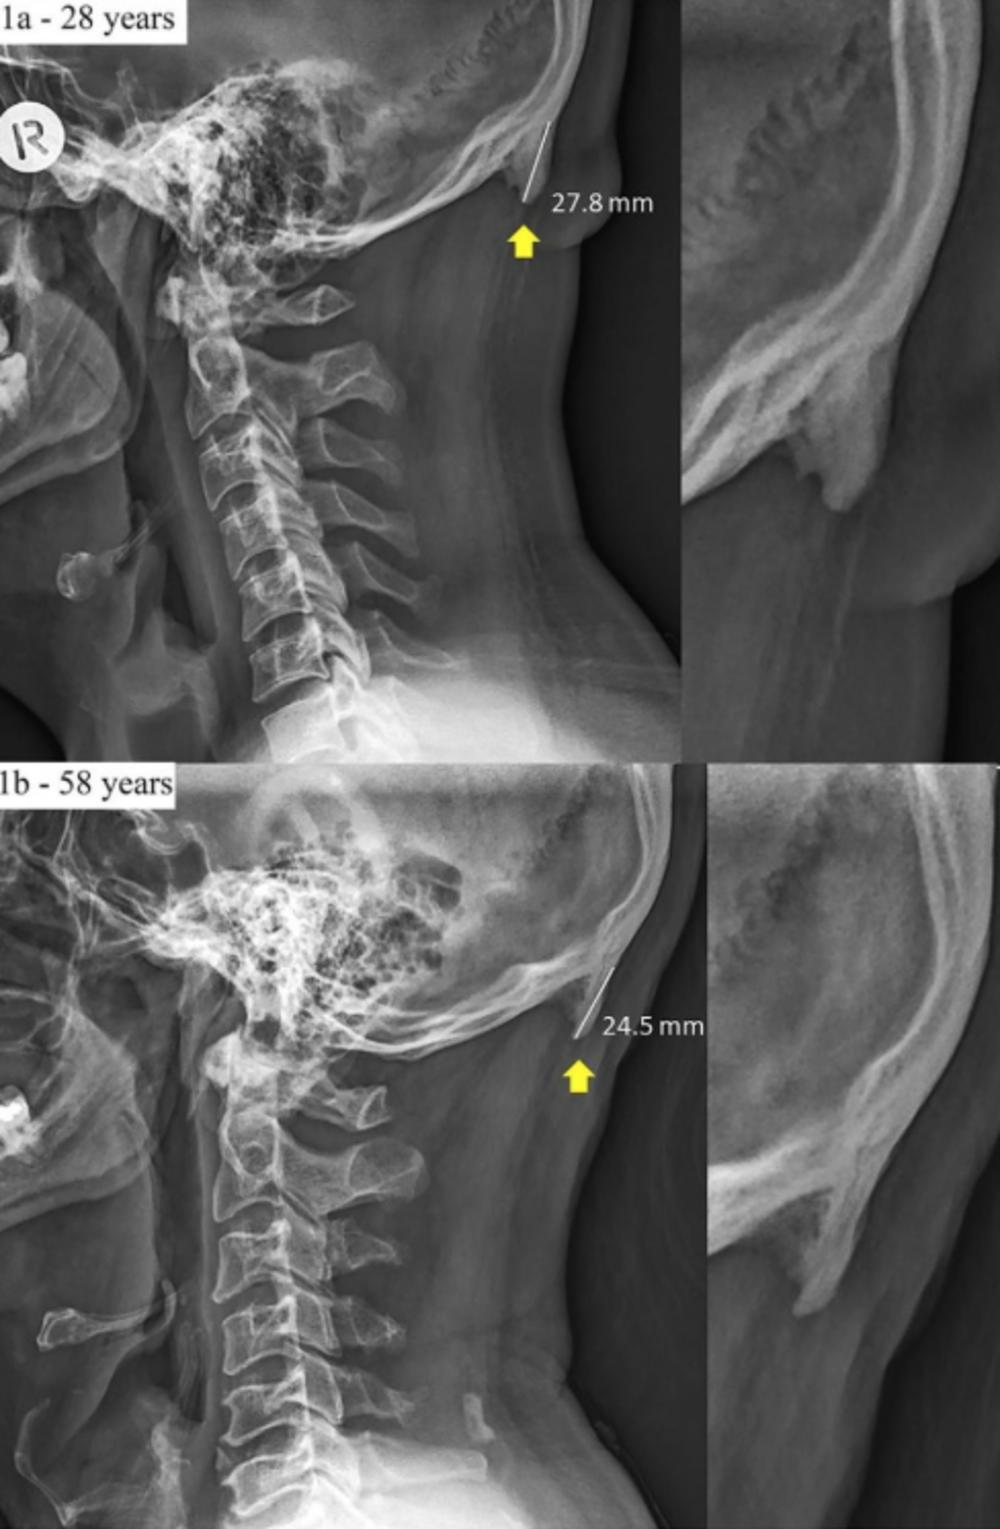

Slike sa rentgena koje su objavil istraživači iz Australije pokazuju da zbog toga što smo stalno pogrbljeni nad telefonom, naša lobanja počinje da razivija dodatni rast kostiju.

Sudeći po njihovoj studiji, sve veći broj ljudi, posebno mlađih, ima izraštaj na dnu lobanje.

Ovaj izraštaj je najčešći kod ljudi starosti između 18 i 30 godina, a izbočine su rezultat načina na koji gledamo ekrane telefona i kompjutera.

Nakon skeniranja više od 1.000 lobanja ljudi starosti između 18 i 86 godina, dr David Šahar sa Univerziteta Sunčane obale u Kvinslendu, tvrdi da je ova promena izazvana dodatnim naporom na delove tela koje ne koristimo često.